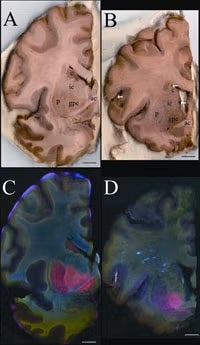

Fig. 2. Metals are increased in the globus pallidus pars externa; A. Gross section of the control forebrain; B. Gross section of the SCA forebrain; C. Overlay of Fe (red), Cu (green) and Zn (blue) distribution of the control forebrain; D. Overlay of Fe (red), Cu (green) and Zn (blue) distribution of the SCA forebrain; c caudate; p putamen; gpe globus pallidus pars externa; ic internal capsule; ac anterior commissure; arrows blood vessels; arrowheads metal rich white matter regions; scale bar=5 mm.

In the SCA sample, the forebrain did not show degenerative changes but the distribution of metals was unusual (Fig. 2). The basal ganglia are huge brain nuclear masses that integrate and regulate the excitatory and inhibitory circuitry adjusting the movement, amongst other functions. The globus pallidus par externa (GPe) is part of the basal ganglia involved in movement inhibition. The GPe of the SCA brain had about 80% more iron than the GPe of the normal brain. The importance of GPe iron in the development or potential treatment of SCA remains to be determined since no obvious cellular degeneration was seen in the GPe.